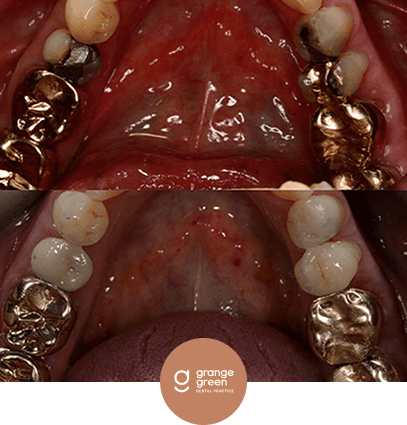

Here are just a few before and after cases to give you an idea of how we help to transform your smile and your confidence using treatments like orthodontics, bridges, veneers and composite fillings…